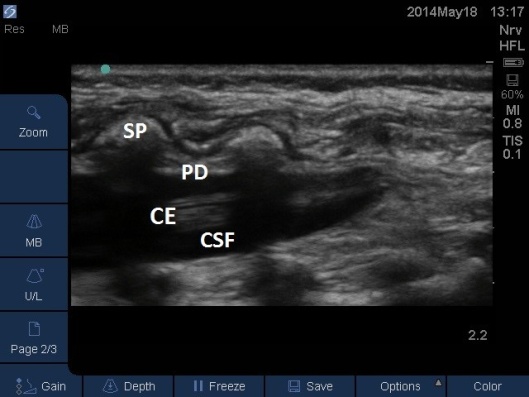

Fig 6. Ultrasound Probe in Midline Longitudinal position over the sacrum. CE = cauda equina. CSF = ceerbrospinal fluid (anechoic), PD = posterior dura (hyperechoic), SP = spinous process.